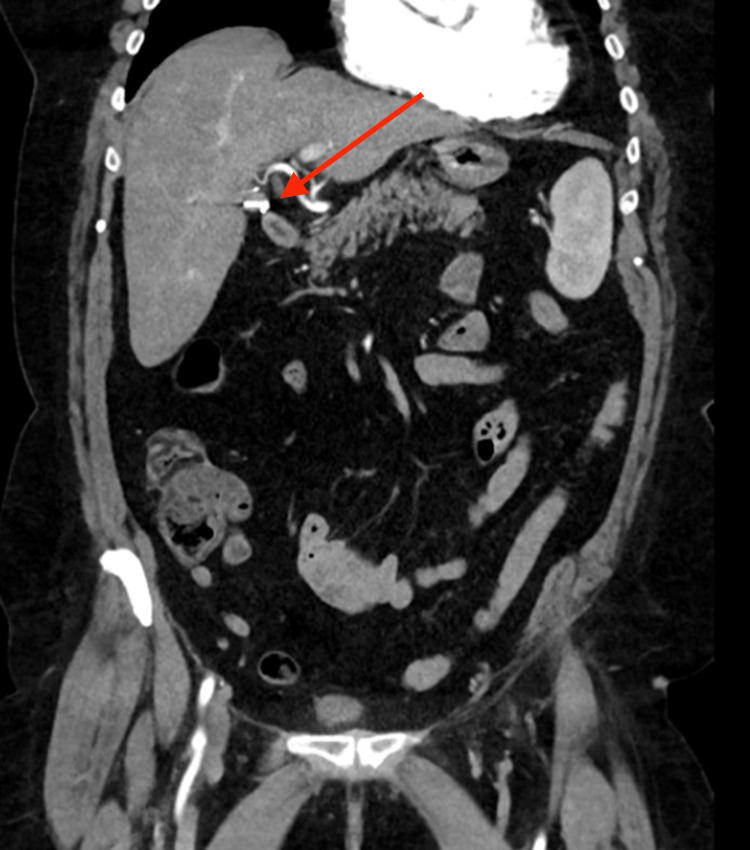

A 70-year-old woman presented to a metropolitan tertiary hospital with acute pancreatitis. This was in the background of a laparoscopic cholecystectomy performed 32 years ago for cholecystitis. She was otherwise well, with no significant past medical history, and reported no alcohol intake. She presented with a two-day history of epigastric pain and vomiting. Biochemical results demonstrated obstructive liver enzymes, with a bilirubin of 151 µmol/L and serum lipase level greater than 1000 U/L. She was investigated with an ultrasound abdomen, computed tomography (CT) abdomen and pelvis, and magnetic resonance cholangiopancreatography (MRCP), all of which did not show choledocholithiasis or cholelithiasis, with a normal biliary system. Of note, the CT also confirmed the previous cholecystectomy with a surgical clip in the expected position (Figure 1). The patient was managed conservatively and discharged a day later following the resolution of her symptoms.

The patient re-presented three weeks later with Charcot’s triad of right upper quadrant pain, pyrexia, and jaundice, suggesting acute cholangitis. Repeat biochemistry results again demonstrated obstructive liver enzymes (gamma-glutamyltransferase (GGT) 400, alkaline phosphatase (ALP) 260), hyperbilirubinemia (90 µmol/L)), and an elevated serum lipase level of 6500 U/L. She was also bacteremic. Blood cultures were positive for Streptococcus mutans. Another CT abdomen and pelvis was performed, and this demonstrated surgical clips that were placed during the cholecystectomy had displaced, eroded, and migrated into the distal CBD with resultant proximal extrahepatic and intrahepatic duct dilatation (Figure 2).